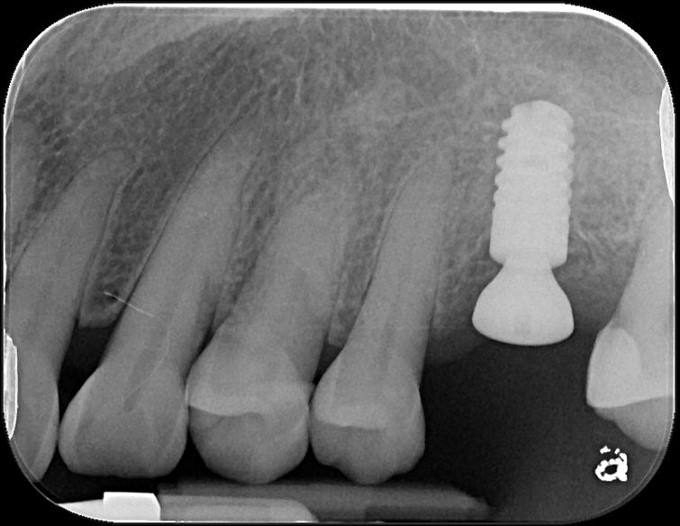

植牙後,角度良好

6個月後植牙骨整合